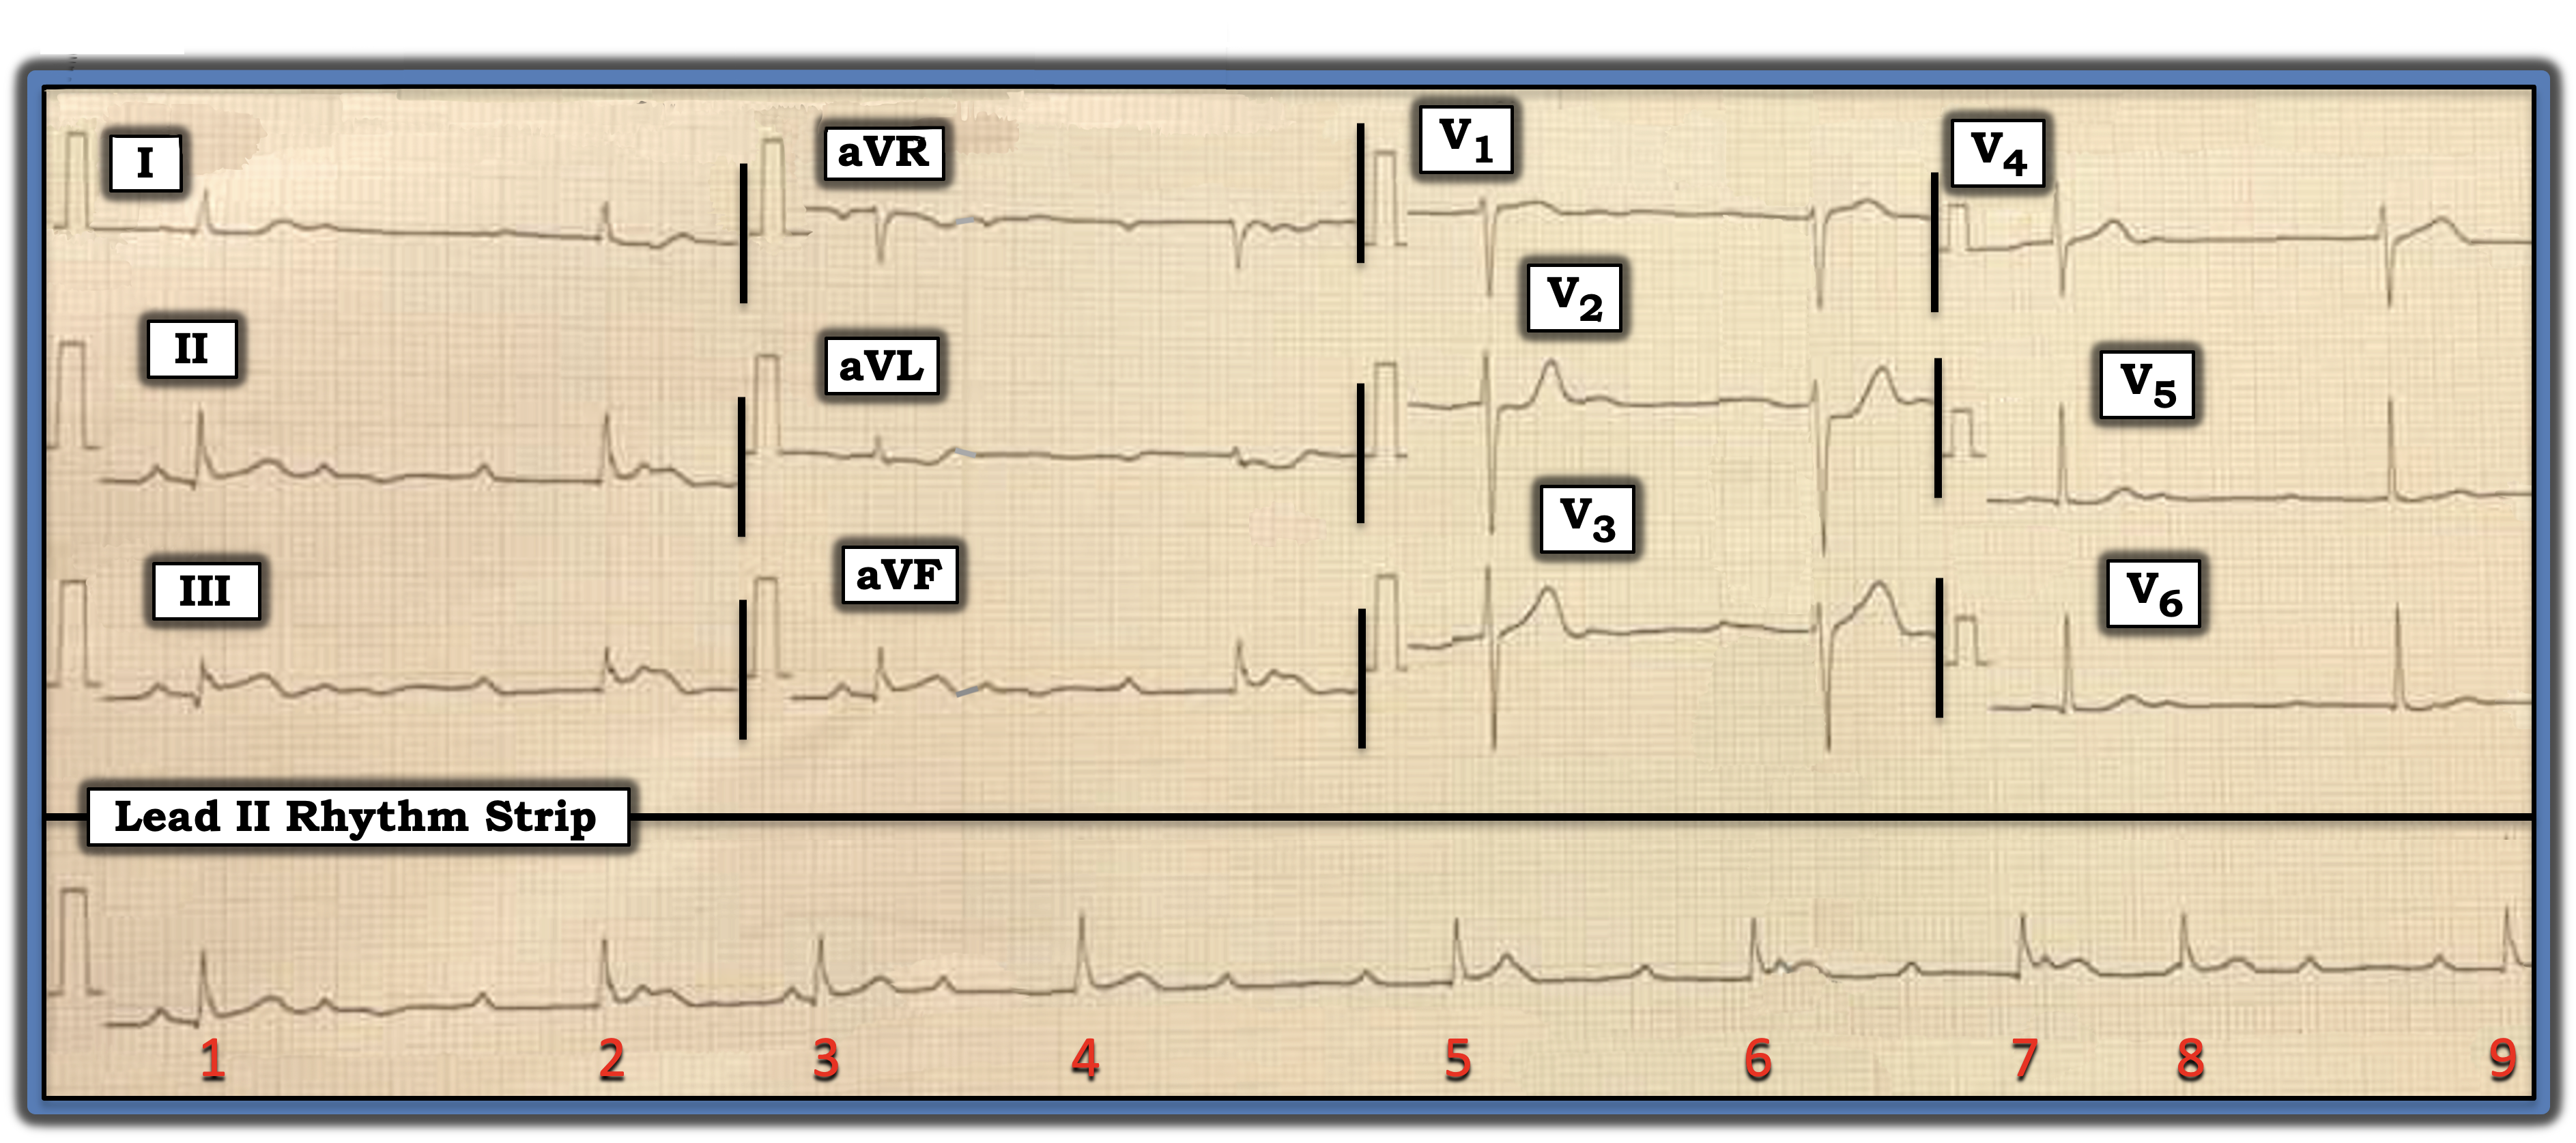

The patient whose electrocardiogram (ECG) is shown below presented for care because of chest pain. Looking at this ECG, can you determine why?

- The long lead II rhythm strip is remarkable for its bradycardia. The QRS complex is narrow, and it appears that there are regular upright P waves — many of which are not conducted. This suggests some significant degree of AV block.

- Despite the fact that the PR interval continually changes, this rhythm is unlikely to be complete (third-degree) AV block. This is because, most of the time, when the rhythm is third-degree AV block, the ventricular rate of the escape pacemaker will be regular.

As a result, I’m happy in my brief initial look at the rhythm to appreciate that there is some complex form of “high-grade” second-degree AV block — with marked bradycardia — and several places where consecutive sinus P waves are not conducted.

- The key leads are III and aVF — both of which show subtle-but-real ST elevation with a hint of terminal T wave inversion. Given this finding in these two inferior leads, there is no doubt that, despite the tiny QRS amplitude in lead aVL, the mirror-image opposite ST-T wave shape in lead aVL compared to the ST-T wave shape in lead III constitutes enough of a reciprocal change in a patient with new chest pain to confirm acute inferior infarction until proven otherwise.

- Knowing that acute inferior myocardial infarction is so commonly associated with acute posterior involvement serves to next focus my attention on leads V2 and V3. Normally, there is slight, gently upsloping ST elevation in these two anterior leads. Therefore, the “shelf-like,” flattened ST segment accompanied by a taller-than-expected T wave in lead V2 immediately suggests associated posterior infarction until proven otherwise.

To emphasize, the cardiac rhythm in today’s case is complex and defies rapid interpretation. That said, “Common things are common.” Acute inferior infarction commonly is associated with some form of AV Wenckebach conduction (especially when the QRS complex is narrow, as it is in today’s case).

Therefore, my “quick initial impression” of today’s tracing is that there is acute infero-postero infarction with some form of resultant high-grade second-degree Wenckebach. This patient is in need of prompt cardiac catheterization with percutaneous coronary intervention to restore flow to the occluded “culprit” artery.